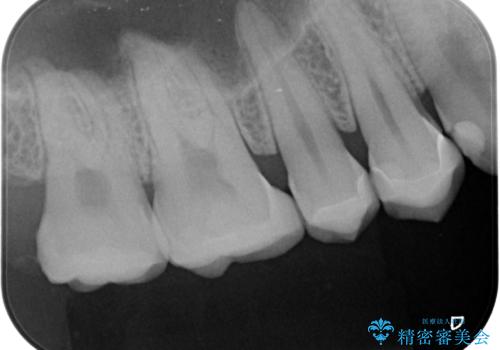

- 銀の詰め物をやりかえたいとの事で来院。

詰め物を外し、虫歯がない事を確認してからe-maxインレーで治療しました。

白く、適合の良い詰め物が入りました。セラミックは汚れや細菌付着しにくいので虫歯の再発のリスクが低くなります。